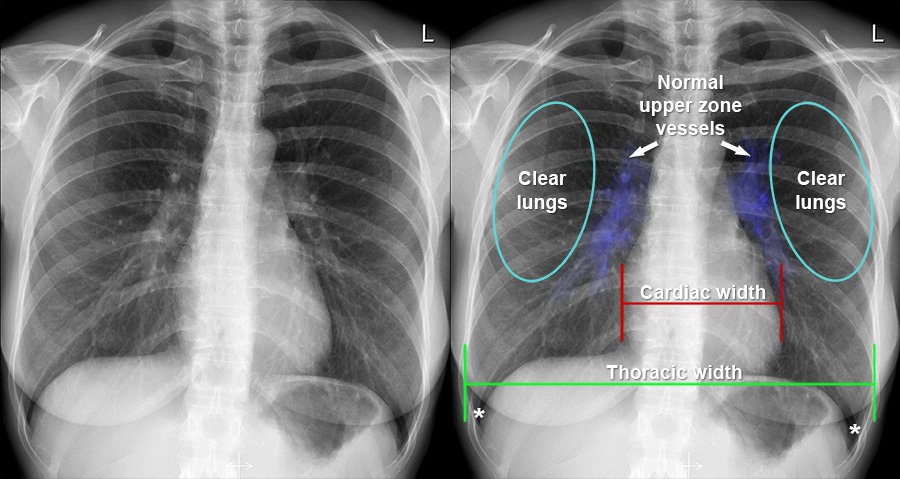

ECG, Digital X-Ray, Ultrasound (USG), Physiotherapy & General Healthcare Services.